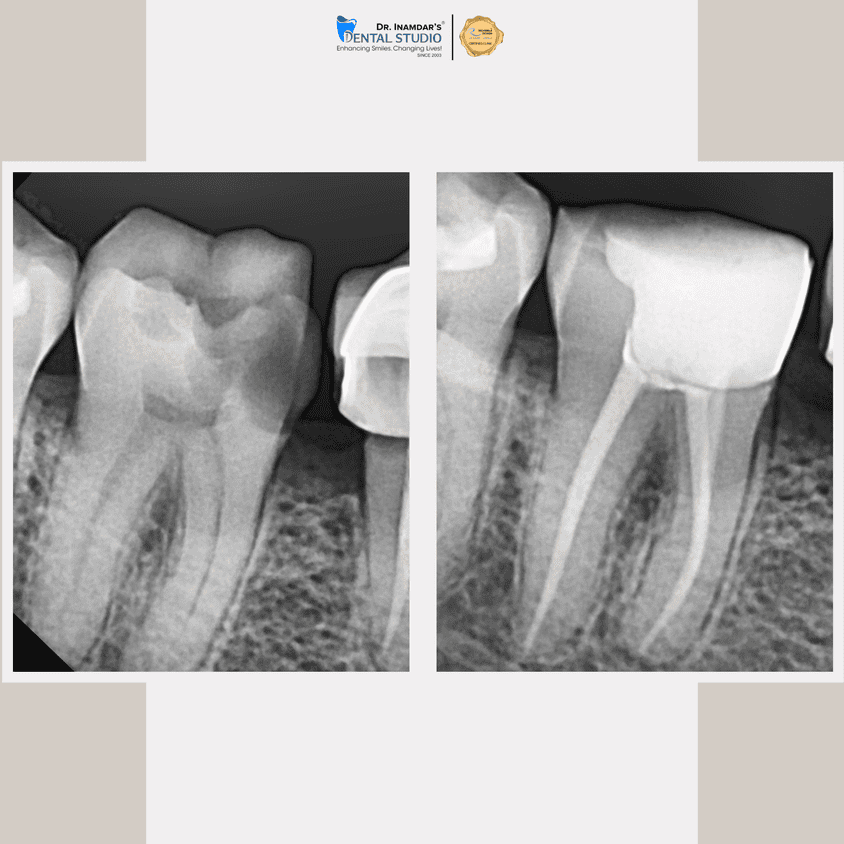

We begin with a detailed dental examination and digital X-rays to identify the source of infection.

The infected tissue is gently removed, and the tooth is thoroughly cleaned and disinfected.

The tooth is sealed and usually protected with a crown to restore strength and function.